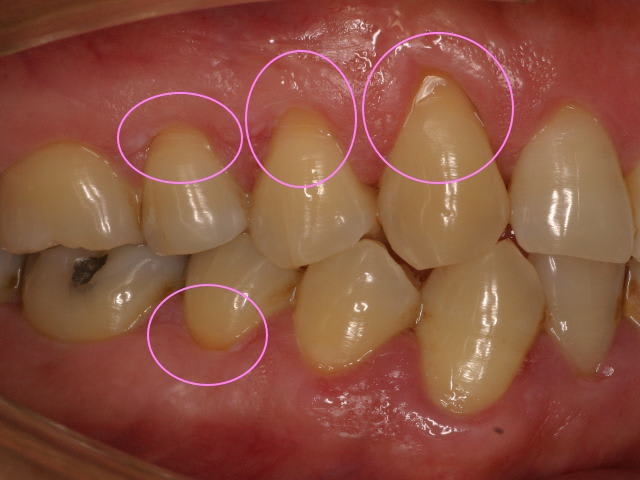

歯がしみる!!

虫歯ができてしまったかも…。と心配される方も多いと思います。

しみる症状は虫歯からだけとは限りません。

冷たいものがしみる、キーンとする、歯ブラシの毛先をあてるとしみる

などの症状に知覚過敏という病状があります。

歯は硬いエナメル質と内側に象牙質、中心に神経があって成り立っております。

なんらかの原因により象牙質が露出すると象牙質には象牙細管という細かい管が神経に向かっており

、その象牙細管から中の神経に冷たいものなどの刺激が伝わり痛みに感じます。これが知覚過敏です。

原因は歯肉の退縮、エナメル質の摩耗などによりおこります。

強く歯ブラシをあてることにより歯肉がさがり、歯の根元の象牙質が削れる

、歯ぎしりで歯が摩耗する、かみ合わせによるものが原因でおこります。

治療法は象牙細管を封鎖させる硝酸カリウム入りの歯磨き剤を使用したり、

症状が強い場合は象牙質の表面にコーティング剤を塗布したり、詰め物をしたりします。